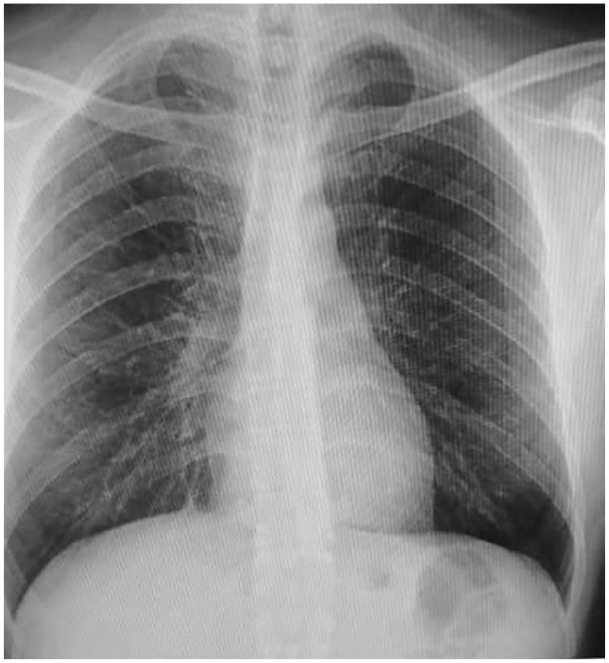

Case presentation: A 42-year-old man with a cystic lesion in his pancreatic tail who had no notable medical history was seen. The diagnosis of a pancreatic hydatid cyst was validated by serological testing and diagnostic imaging techniques.

Clinical discussion: Due to their uncommon nature, the differential diagnosis of pancreatic hydatid cysts can be challenging. Imaging modalities such as computed tomography (CT), magnetic resonance imaging (MRI), and ultrasound are important for identifying characteristic features. Serological testing further aids in confirming the diagnosis. Treatment typically involves a combination of medical and surgical approaches. Antiparasitic drugs, such as albendazole or mebendazole, are administered to kill the parasite. Surgical intervention is necessary to remove the cyst and reduce the chance of recurrence and complications.